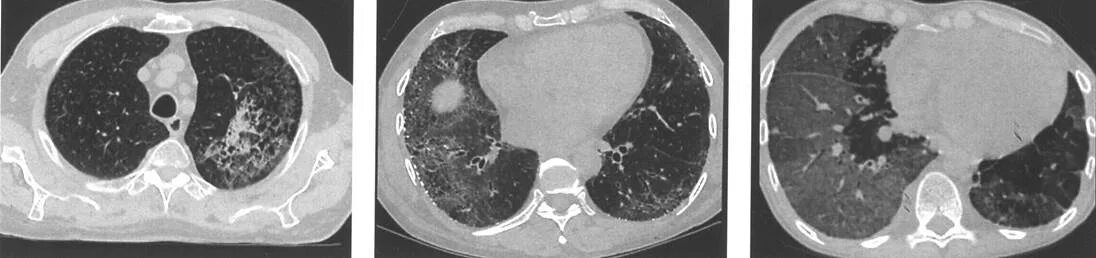

Фиброз кт